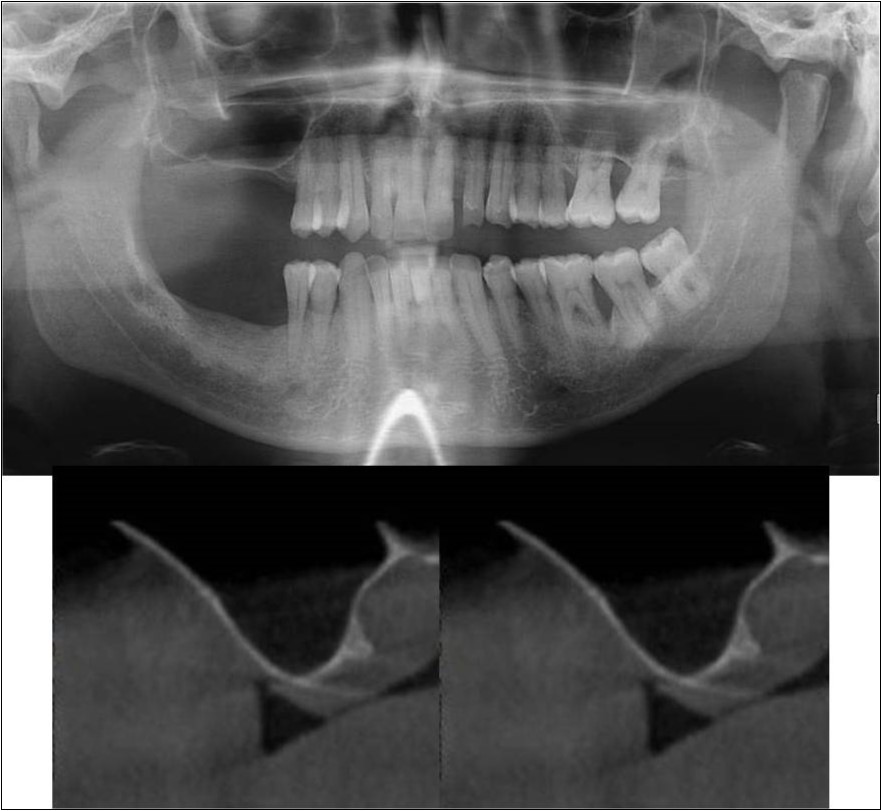

Figure 7.(a-c) Pre-treatment OPG and cross sections of CBCT showing residual alveolar bone height for Case No.1;

Figure 8.(a-c) Post-treatment OPG and cross sections of CBCT showing residual alveolar bone height for Case No.1;